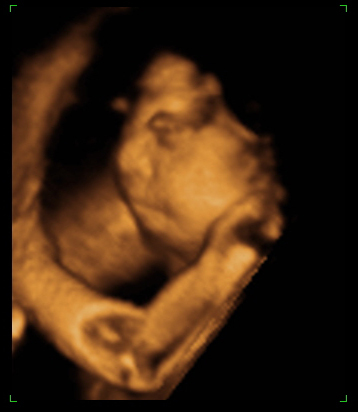

The purpose of this website is to give people who have found out their fetus is suffering from Anencephaly, somewhere to find out information about this condition.